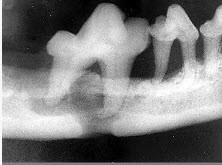

颌面外伤患者,咬合错乱,下唇麻木张口受限,经X线检查如图。应该为()

A、上颌骨骨折

B、颧骨骨折

C、颧弓骨折

D、下颌骨骨折

E、牙槽突骨折

D